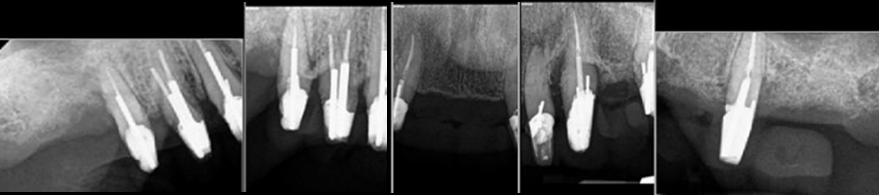

When all of a patient’s teeth are failing but dentures aren’t an option, we perform “staged therapy.” First, every tooth is prepared and fitted with a full-arch temporary splint (Fig. 1). Next, select teeth are extracted and replaced with implants, while the remaining teeth continue to hold the temporary (Fig. 2 & 3). In Stage II, abutments are seated on existing implants, the remaining teeth are extracted, and implants placed (Fig. 4). Finally, a permanent fixed splint is secured on all implants (Figs. 5 & 6).

Fig. 1: Failing Teeth Briefly Used to Hold a Temporary Splint

Stage I: Clean up the decay on all of her remaining upper teeth, prepare them (Fig. 1) and insert an aesthetic temporary splint (Fig. 2). This was followed by the strategic extraction of several teeth, replacing them with implants, while the remaining teeth held the temporary bridge (Fig. 3).